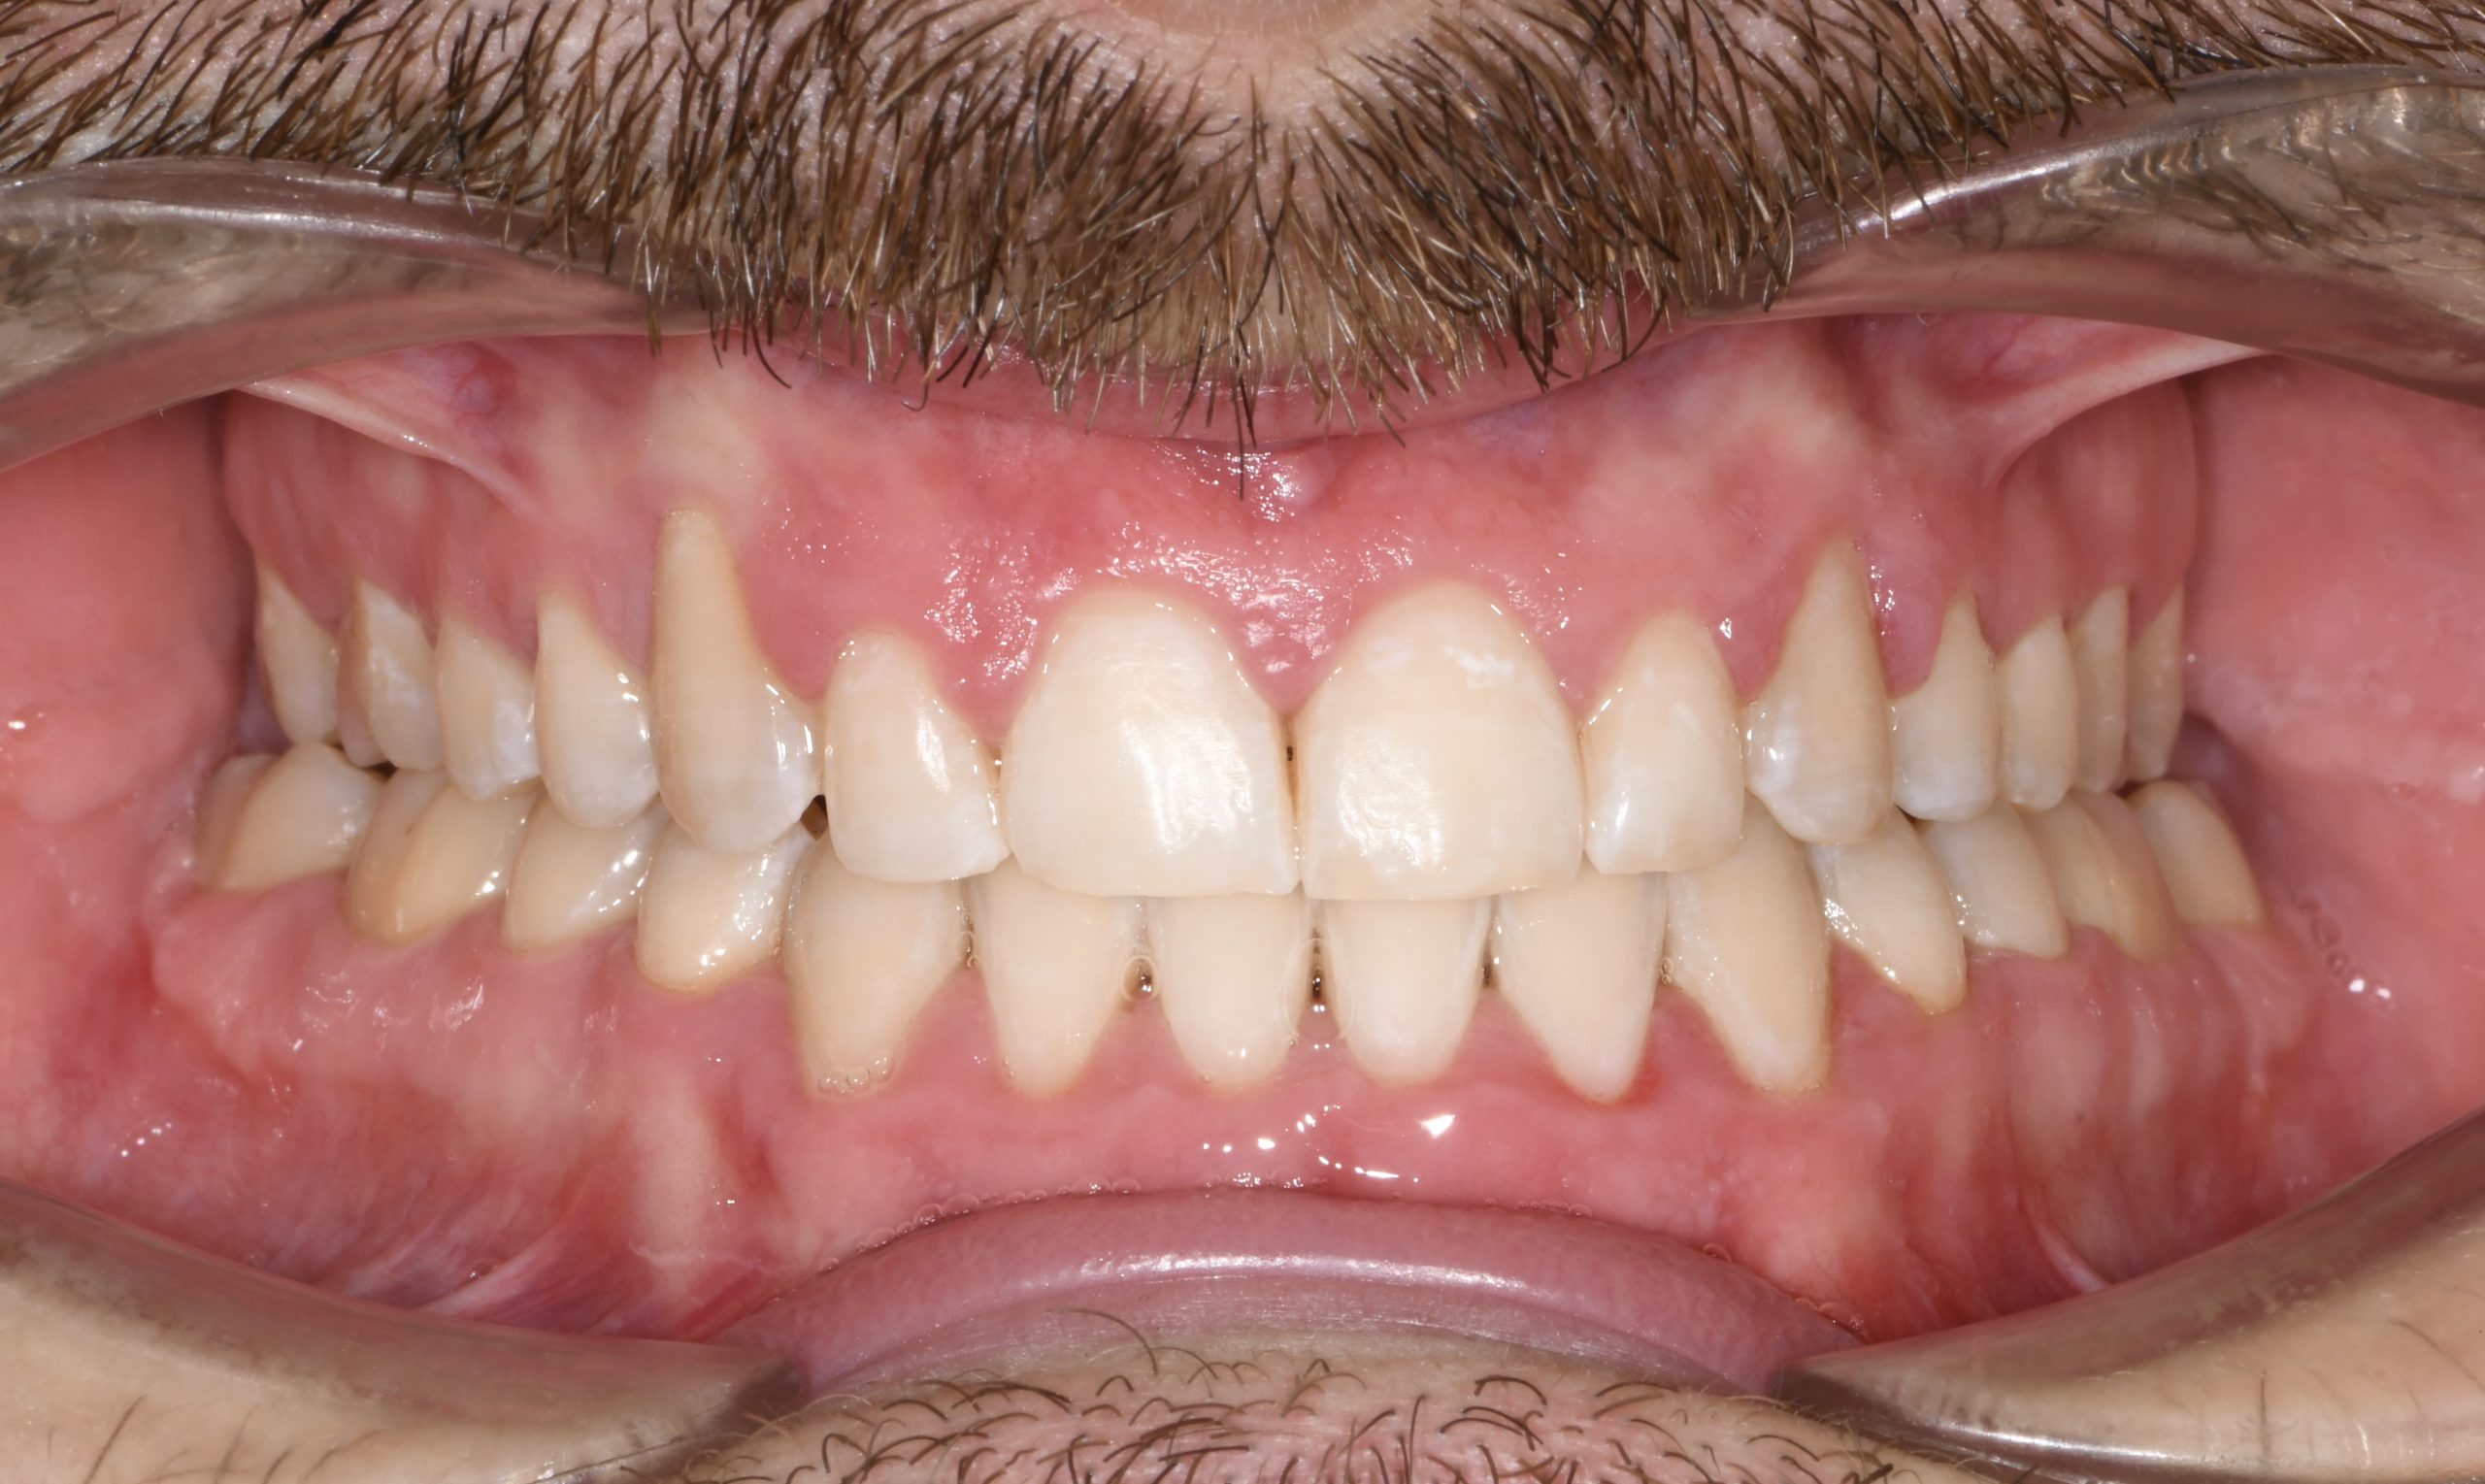

Az elmúlt évekből rengeteg szakmai referenciát tudnánk bemutatni, amelyek különböző fogszabályozási problémákat oldottak meg. Válogatva a több száz esetből, ezen az oldalon olyan képeket, információkat igyekeztünk bemutatni, amelyeknek a segítségével a jövőbeni pácienseinknek azt tudjuk üzenni: A Te fogsorod is lehet gyönyörű!

(Képeket a Pácienseink külön írásos beleegyezésével mutatjuk be!)